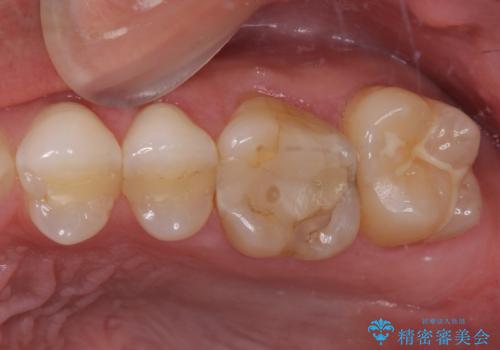

- 奥歯の詰め物が外れてしまったとのことで来院された患者様です。

幾度も詰め物治療を行ったため継ぎ接ぎだらけとなっていたため、インレーにて修復治療をすることとしました。

咬合力が強いため、ゴールド合金(PGA)のインレーを選択することとしました。